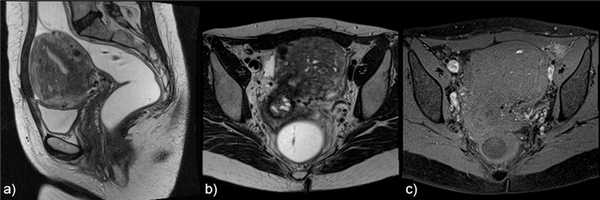

![]()

Рис.9 Внешний вид "швейцарский сыр" а) аксиальный T1 3D FS, b) корональный T2 и с) сагиттальный T2, показывающие плохо отграниченную, утолщенную переходную зону с наличием в миометрии большого количества железистых кист, узелков и линейных бороздок.

Рис.10 Аденомиома. Сагиттальное T2 взвешенное изображение, отграниченная гипоинтенсивная масса в толще миометрия с нечеткими контурами, мелкими гиперинтенсивными фокусами в структуре и минимальным масс-эффектом.

Рис.11 Полиповидная аденомиома: а) саггитальные Т2 и b) аксиальные Т2 взвешенные изображения, шаровидной формы участок переходной зоны с нечеткими контурами, выступающий в полости матки.

Рис.12 Изолированная или ювенильная кистозная аденомиома: а) и b) сагиттальные с) корональные T2-взвешенные изображения, шаровидное образование с центральной полостью, имеющей гиперинтенсивный сигнал, не связанное с полостью матки; в остальном матка нормальная.